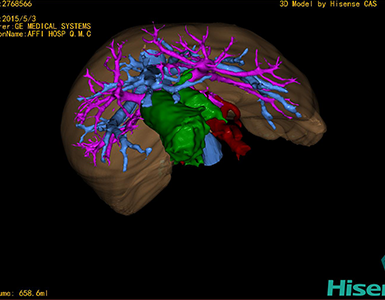

CT结果输入海信CAS系统后行3D重建及手术规划后,于2015-5-6全麻下行“胆总管囊肿切除+胆囊切除+胆总管-空肠吻合术”手术治疗:

术前三维重建及手术方案设计:

将0.625mm双源薄层CT资料的静脉期和动脉期Dicom格式文件导入海信CAS系统。

通过调节窗宽窗位调整CT序号,对肝实质,胆囊,下腔静脉,肿瘤,肝动脉、门静脉及肝静脉等进行三维重建;系统自动计算肝脏体积。

术前手术方案的规划。

术前三维重建:

重建图片